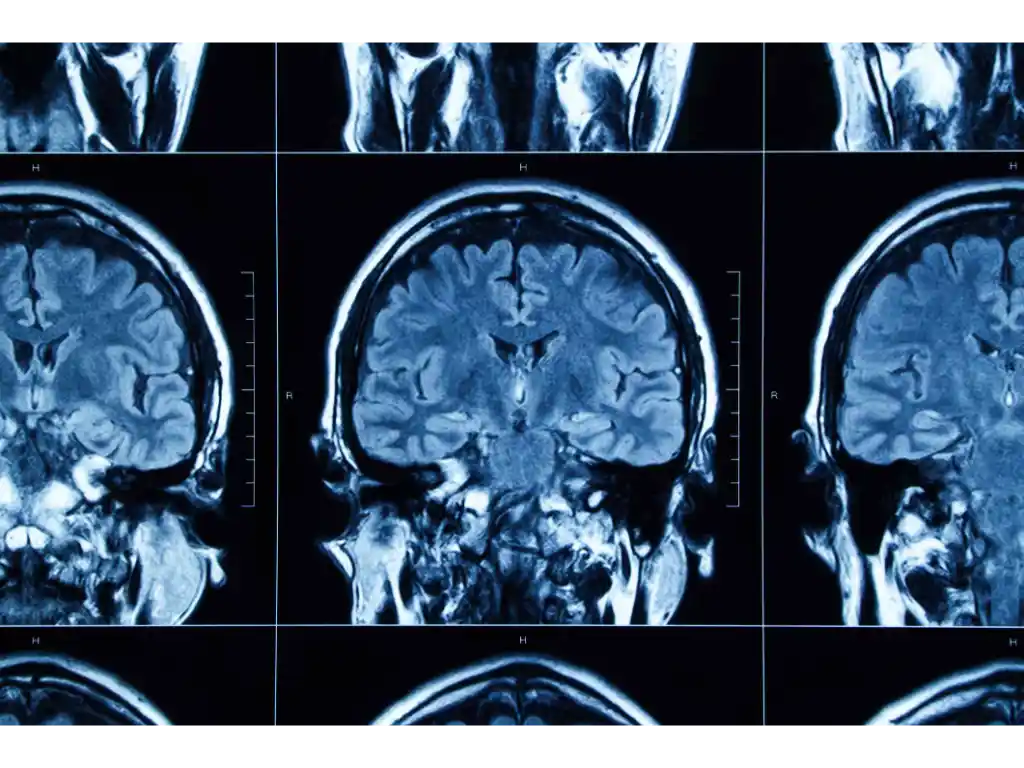

The scientists involved with the study say TBI is a worldwide public health issue, killing or debilitating at least three million people each year. About one-third of patients hospitalized with a TBI pass away from brain damage that occurs weeks or months after suffering the initial injury. TBI survivors also have an increased risk of dementia and cognitive decline. While ongoing inflammation in the brain parallels the ongoing damage and loss of function, standard anti-inflammatory therapies don’t help to really improve patients’ outcomes. Researchers say that therapies that target and decrease sources of increased inflammation following a TBI, such as the ILC subtypes ILC1 and ILC3 are needed.

Within a day of injury, researchers observed increases in all three ILC subtypes in the meninges of the TBI model. The meninges is the covering of the brain and spinal cord. Researchers also found that ILC2 and ILC3 levels remained higher a year after the injury, along with chronic inflammation and a 50% reduction in activation of AMPK. Researchers also observed ongoing problems with energy use.

Similar patterns of increased proinflammatory ILCs were found in the dura and the cerebral spinal fluid of patients who suffered a moderate to severe TBI. These patients needed a decompressive craniectomy to relieve pressure on their brains. Patients with hydrocephalus had lower levels of ILC cerebrospinal fluid.